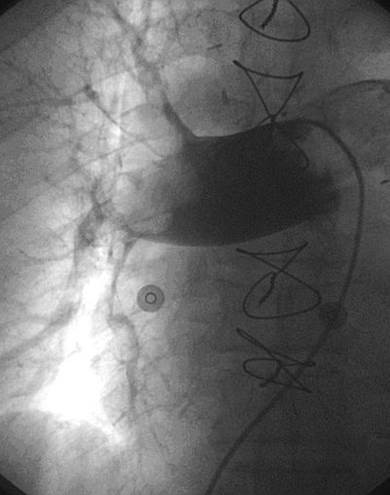

Angiografía de la arteria pulmonar izquierda realizada con un catéter en espiral de 6 F en ángulo, que demuestra la presencia de un trombo dentro de la arteria pulmonar izquierda y en las bifurcaciones lobulares intermedia, inferior y superior.

Se efectuó una trombectomía reolítica con el catéter PE de AngioJet® mediante un catéter guía multifunción de 8 F y una guía de angioplastia hidrófila de 0,035’’.

Angiografía pulmonar izquierda realizada tras una trombectomía reolítica en la que se muestra la mejora del índice de perfusión y obstrucción.